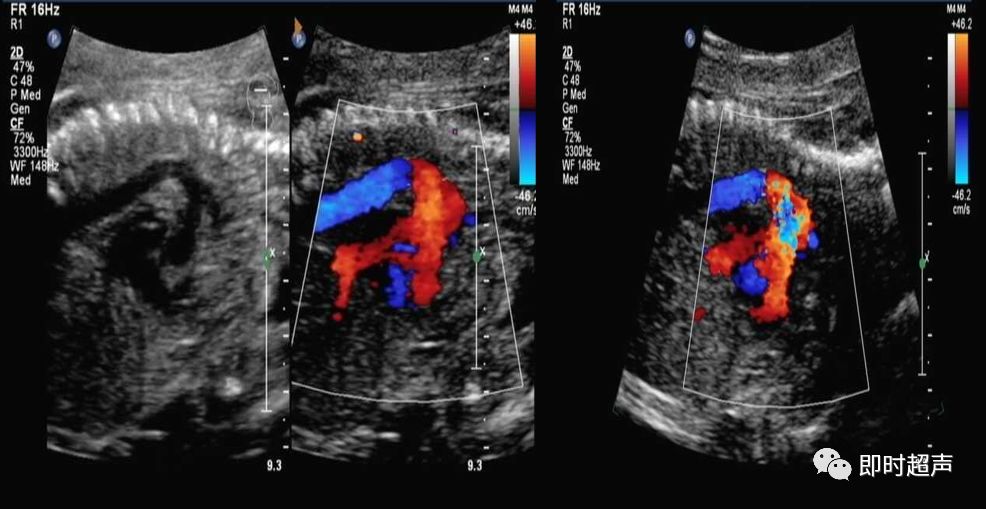

血管数目增多1:双上腔静脉、肺静脉异位引流(心上型)、伪像

如何鉴别永存左上腔静脉和肺静脉异位引流?

- 观察肺静脉有无开口进入左心房

- 追踪观察异常血流引流途径,是进入右上腔静脉还是心房

永存左上腔静脉